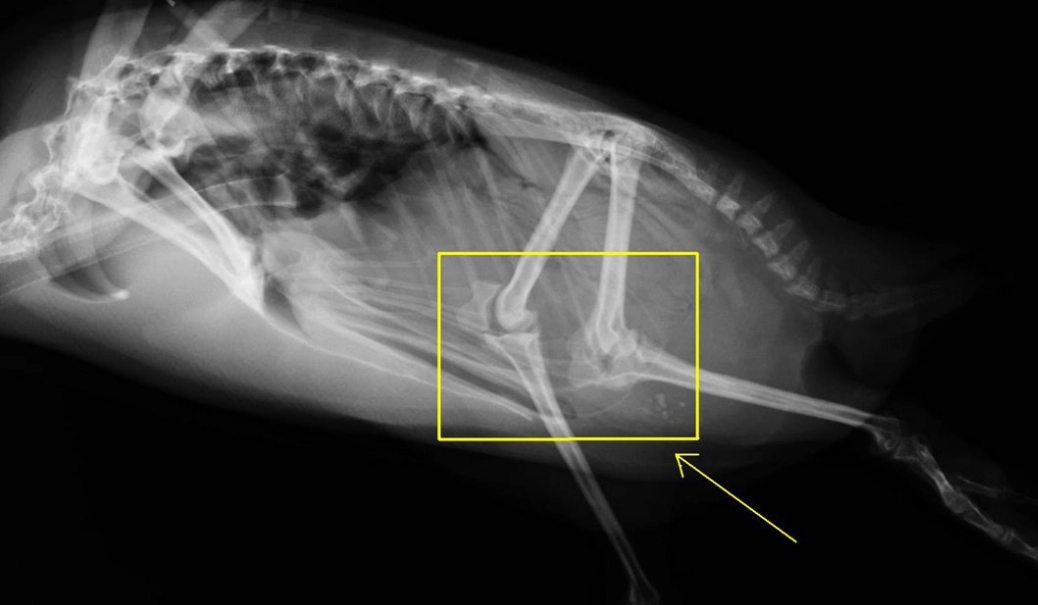

У пингвинов есть колени